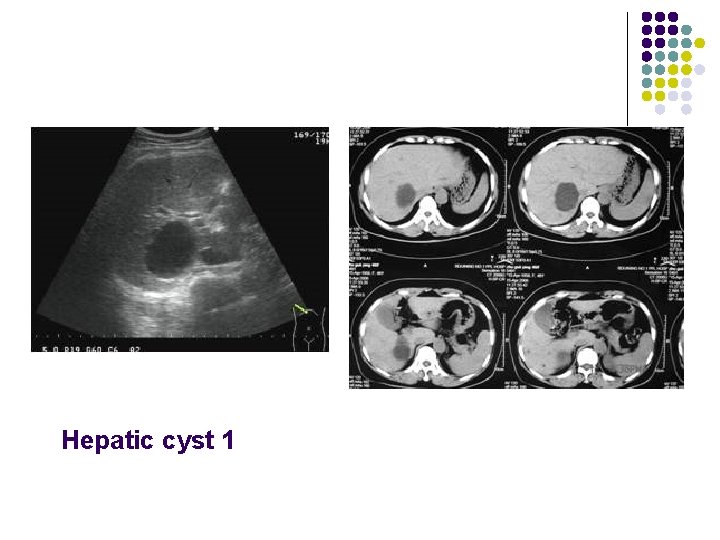

Ultrasound Findings of Cystic Lesions On ultrasound examination the cyst walls are thin , with well-defined borders, and anechoic with distal posterior enhancement.

Sonographic Features Of hepatic cyst: l No internal echoes l Smooth borders l Regular /irregular outline l Acoustic enhancement l Septum may be seen

Hepatic cyst 1

Hepatic cyst Second most common benign hepatic lesion(22%) l Acquired hepatic cyst: second to trauma, inflammation , parasitic infection l Associated tuberous necrosis polycystic kidney disease(25 -33%have liver cyst); polycystic liver disease(50%have polycystic kidney disease) l